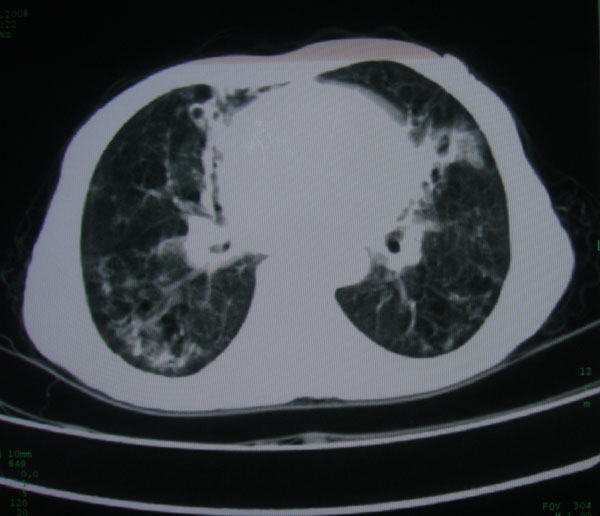

标题: CT15046:F59Y,咳嗽间断咳血丝痰就诊. [打印本页]

咳嗽\间断咳血丝痰就诊.

考虑支气管扩张并感染

1慢支伴感染;右下肺周围型肺癌。

本例应该是“慢性疾病并发多种合并症”即:慢支并感染并支气管扩张征!结合病灶分布 形态分析,不除外合并“继发性肺结核”!

慢性支气管炎伴全小型肺气肿、支气管扩张、感染、间质纤维化。

多考虑支气管扩张并感染,双下肺继发性肺结核不除外

慢性支气管炎伴全小叶型肺气肿、支气管扩张、感染、间质纤维化